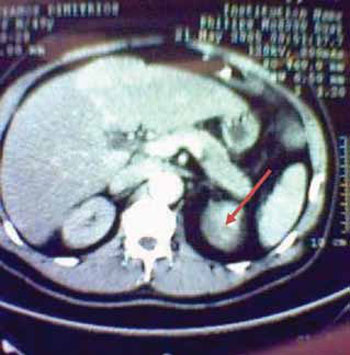

Forty days prior to admission, the patient suffered a severe thoracic pain of abrupt onset that led to urgent admission to another hospital. Computed tomography (CT) and magnetic resonance imaging (MRI) showed an aortic dissection extending from the left subclavian artery to both iliac arteries, as well as a 6 cm left adrenal mass (Figure 1). At the time of urgent admission, renal function was seriously impaired and necessitated hemodialysis (serum creatinine 12.3mg/ dl and blood urea nitrogen 250mg/dl).

Figure 1. Presence of a 6 cm left adrenal mass (arrow).